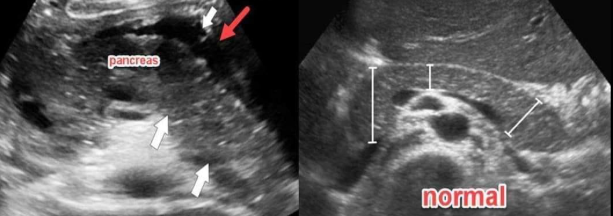

This patient presents with elevated lipase and amylase and leukocytosis. Which form pathology is most likely represented by the arrow in this image?

Focal acute pancreatitis of the pancreatic head

favored over mass due to leukocytosis!!!

What is the red arrow pointing to? Which pancreatic pathology is this sonographic finding associated with?

Peri-pancreatic fluid, pancreatitis